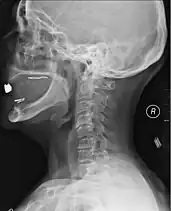

A radiographic evaluation using an X-ray, CT scan, or MRI can determine if there is damage to the spinal column and where it is located.[15] X-rays are commonly available[60] and can detect instability or misalignment of the spinal column, but do not give very detailed images and can miss injuries to the spinal cord or displacement of ligaments or disks that do not have accompanying spinal column damage.[15] Thus when X-ray findings are normal but SCI is still suspected due to pain or SCI symptoms, CT or MRI scans are used.[60] CT gives greater detail than X-rays, but exposes the patient to more radiation,[62] and it still does not give images of the spinal cord or ligaments; MRI shows body structures in the greatest detail.[15] Thus it is the standard for anyone who has neurological deficits found in SCI or is thought to have an unstable spinal column injury.[63]